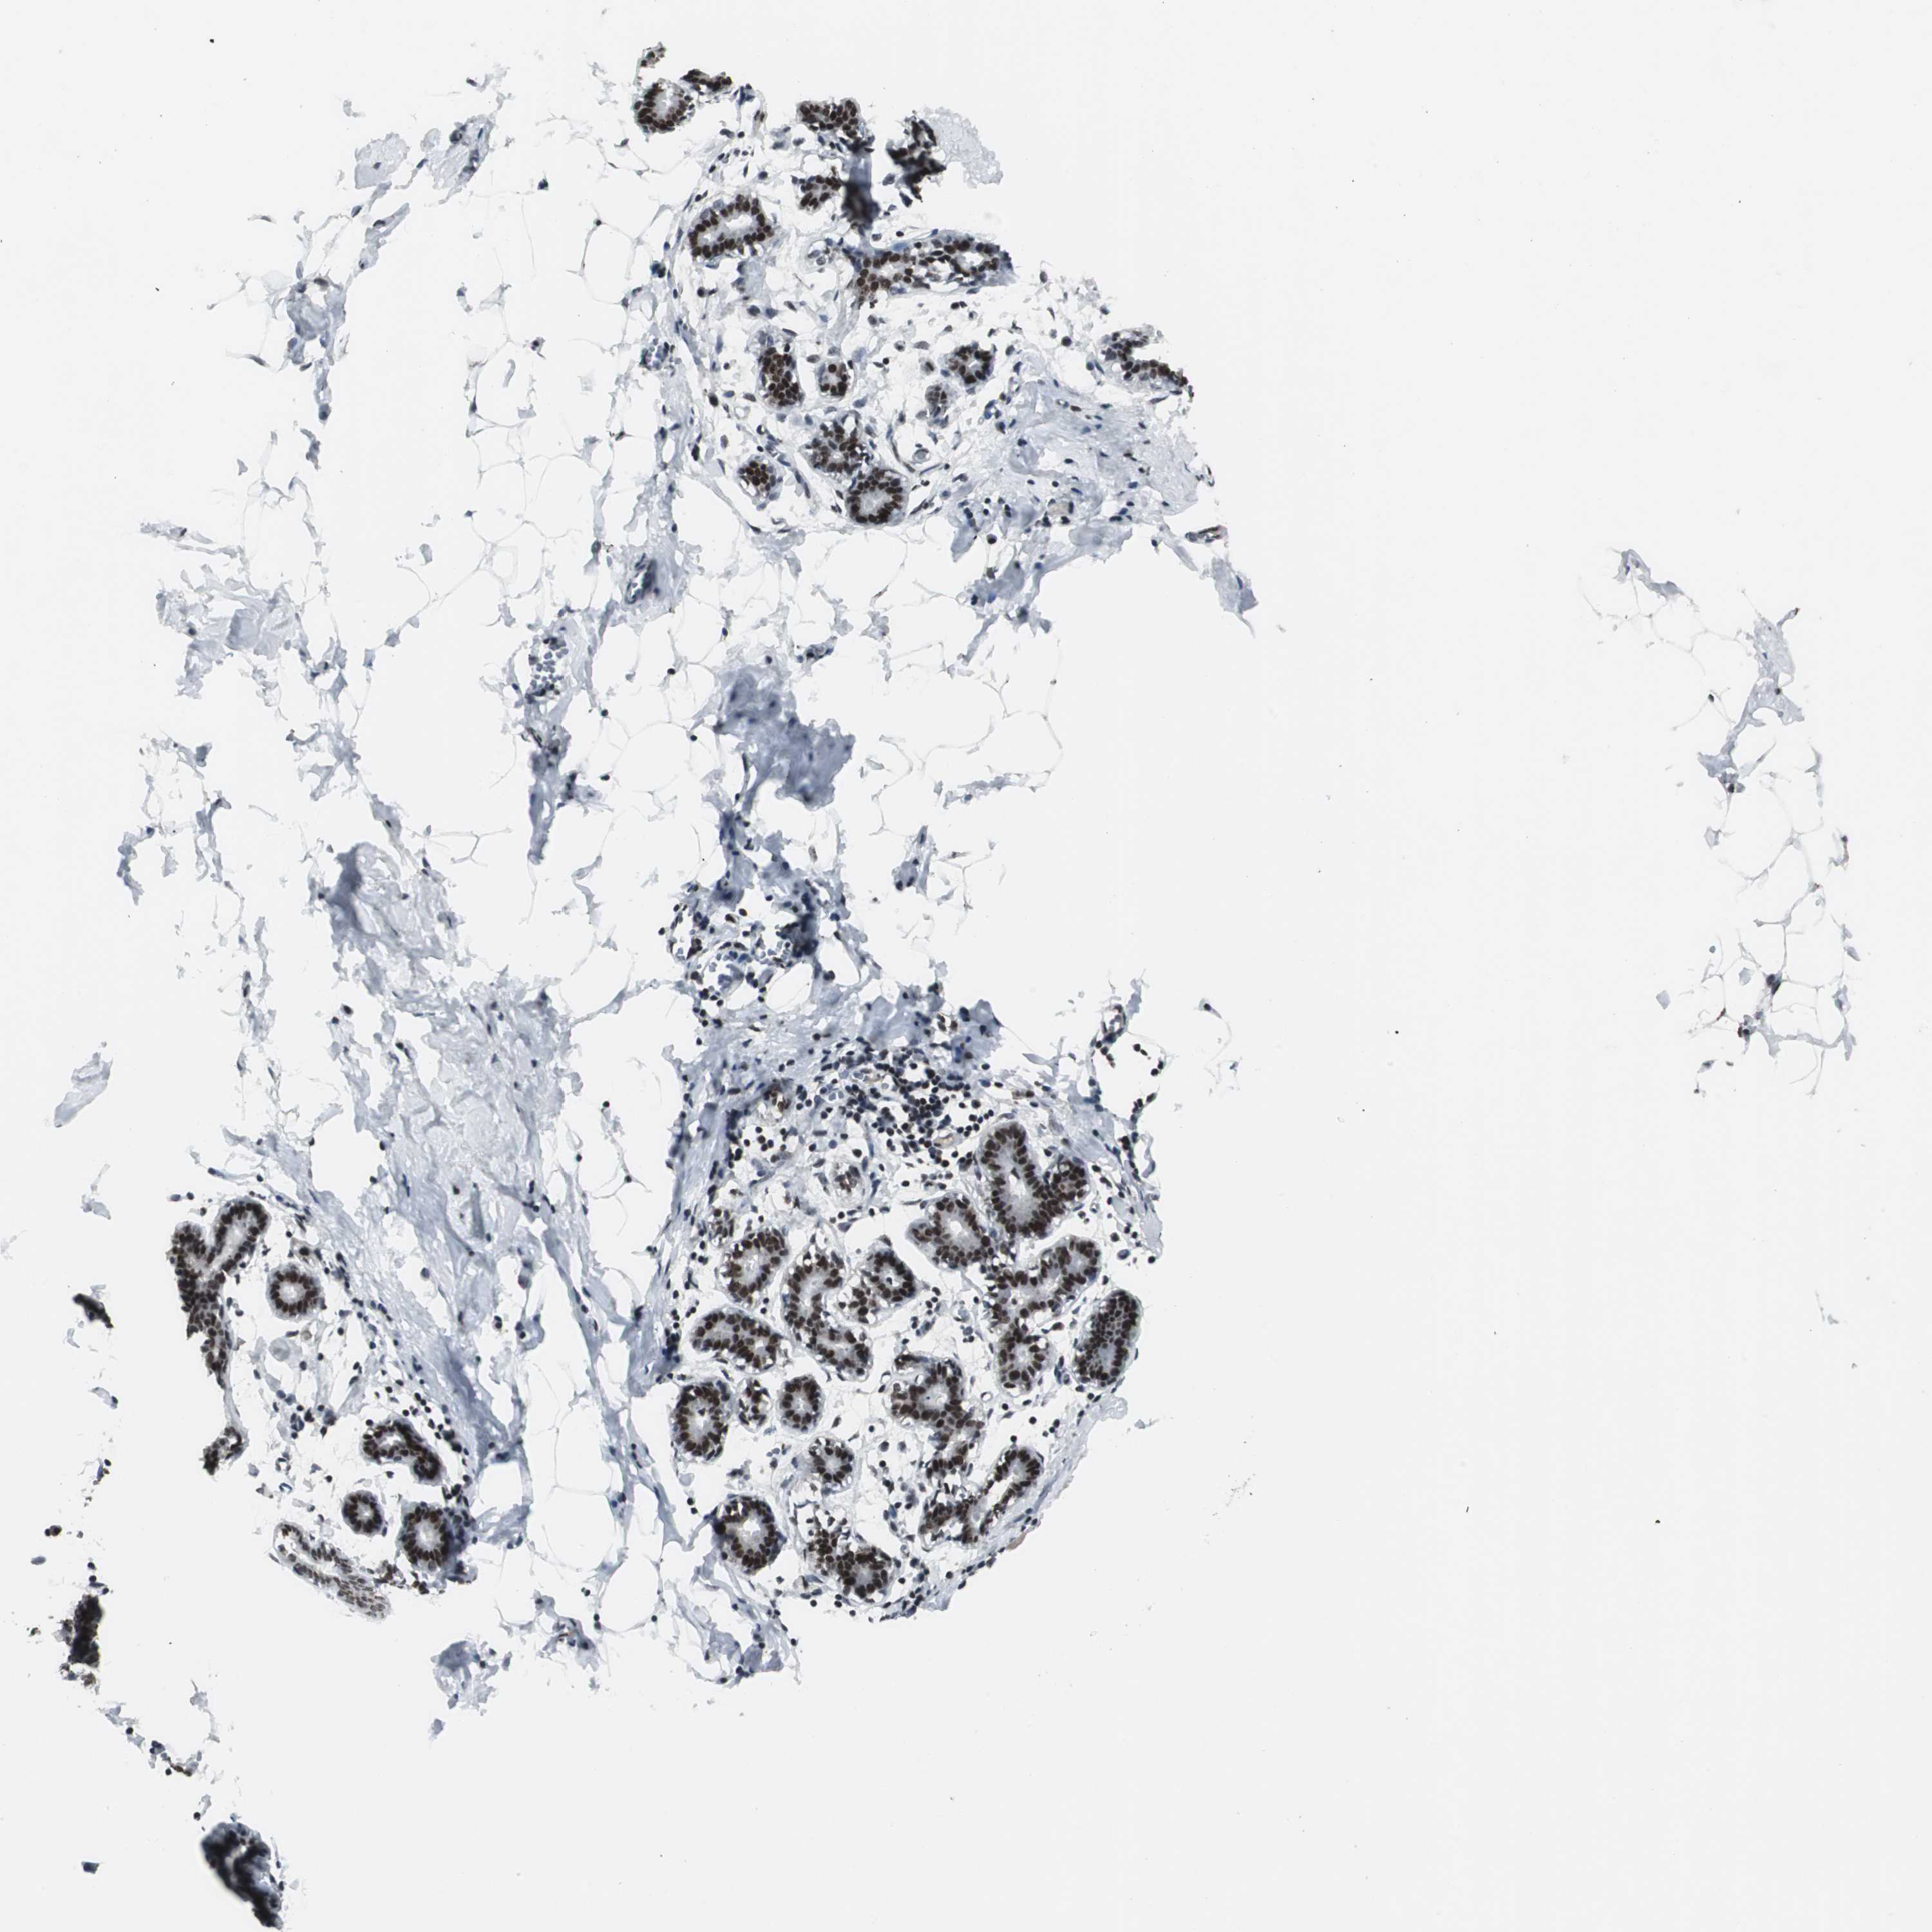

BREAST - Antibody stainingi

Antibody staining in the annotated cell types in the current human tissue is reported as not detected, low, medium, or high, based on conventional immunohistochemistry profiling in selected tissues. This score is based on the combination of the staining intensity and fraction of stained cells.

Each image is clickable and will lead to virtual microscopy that enables deeper exploration of all samples and also displays staining intensity scores, fraction scores and subcellular localization as well as patient and tissue information for each sample.

Antibody HPA006725

Adipocytes Medium

Glandular cells High

Myoepithelial cells Medium